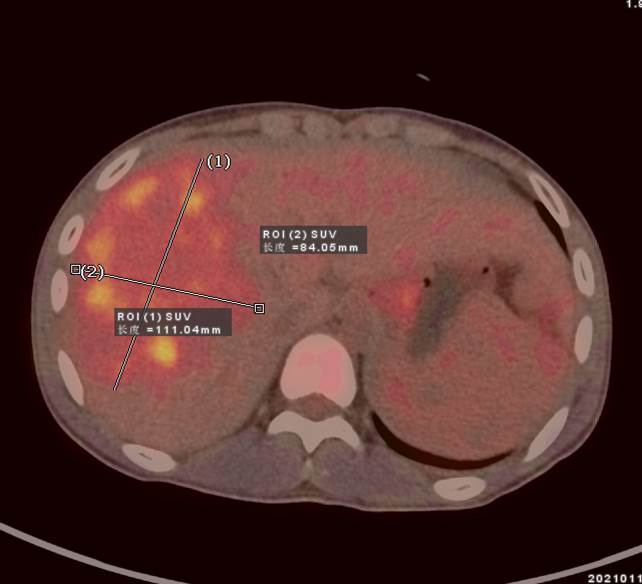

13歲男孩小新,因腹瀉就診,外院CT發(fā)現(xiàn)肝臟多發(fā)占位,考慮肝癌并肝內(nèi)轉(zhuǎn)移,肝硬化、門靜脈癌栓形成。為了查找病因及進行更深入的檢查,小新一家選擇進行全身的PET/CT檢查。據(jù)悉小新有乙肝病史10年。

PET/CT顯示肝臟明顯增大,肝內(nèi)見10.6x8.1cm稍低密度腫塊,F(xiàn)DG攝取不同程度最高,SUVmax 2.5-5.5。門靜脈增寬,F(xiàn)DG攝取不高,脾臟增大。

PET/CT診斷 :原發(fā)性肝細胞肝癌;門靜脈高壓